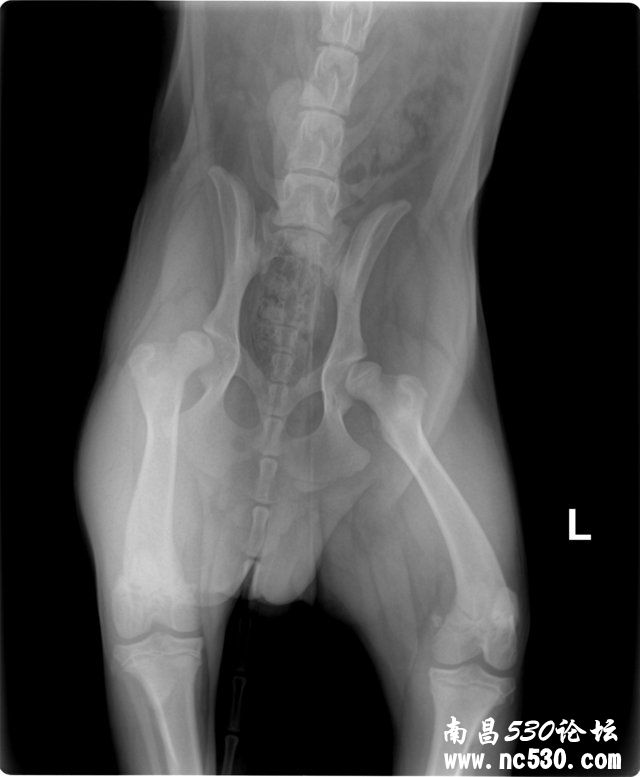

动物种类:狗

动物品种:金毛

动物年龄:6个月

动物性别:公

髋关节问题,麻烦帮办看看!